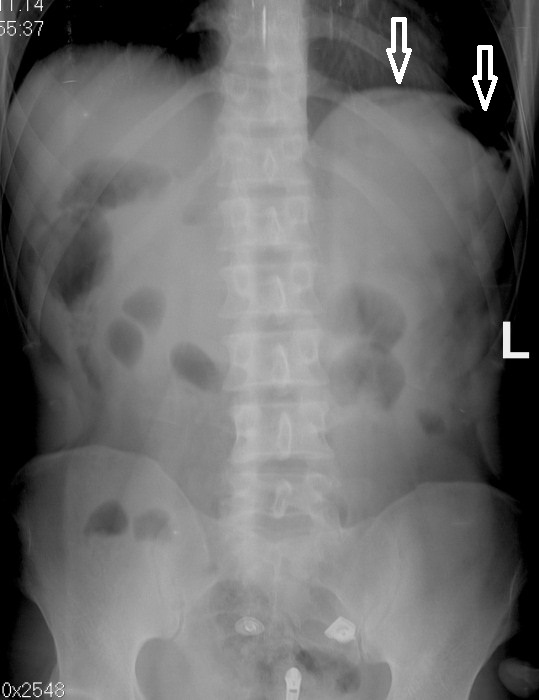

Нормы обзорной рентгенографии брюшной полости